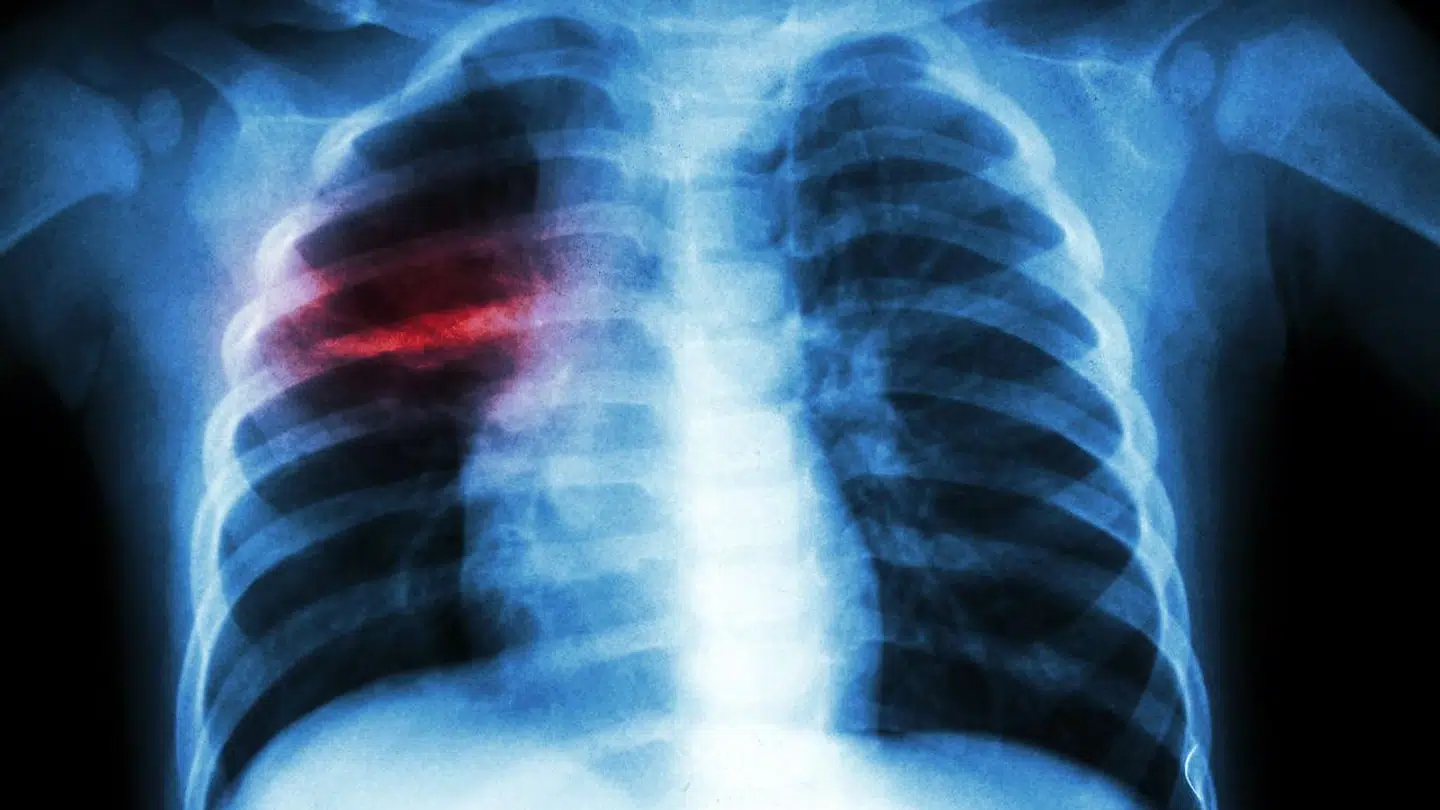

Otte teenagere i en niende klasse på Sofiendalskolen i Haslev på Sydsjælland er blevet smittet med den farlige sygdom lungeturberkulose.

Det er en sygdom, som mange tidligere døde af.

Tuberkulose kan være en farlig sygdom, og den smittede elev har derfor ikke været i skole, siden sygdommen blev opdaget.

Ifølge Lungeforeningen er tuberkulose ikke en særlig smitsom sygdom, men den spreder sig fra person til person, når den smittede nyser eller hoster.

For at blive smittet kræver det, at man er tæt sammen. Smitte kræver, at man er tæt på hinanden i en længere periode, som man typisk er i en familie eller en skoleklasse. Skolelederen har ikke kendskab til, at flere end de otte er blevet smittede.